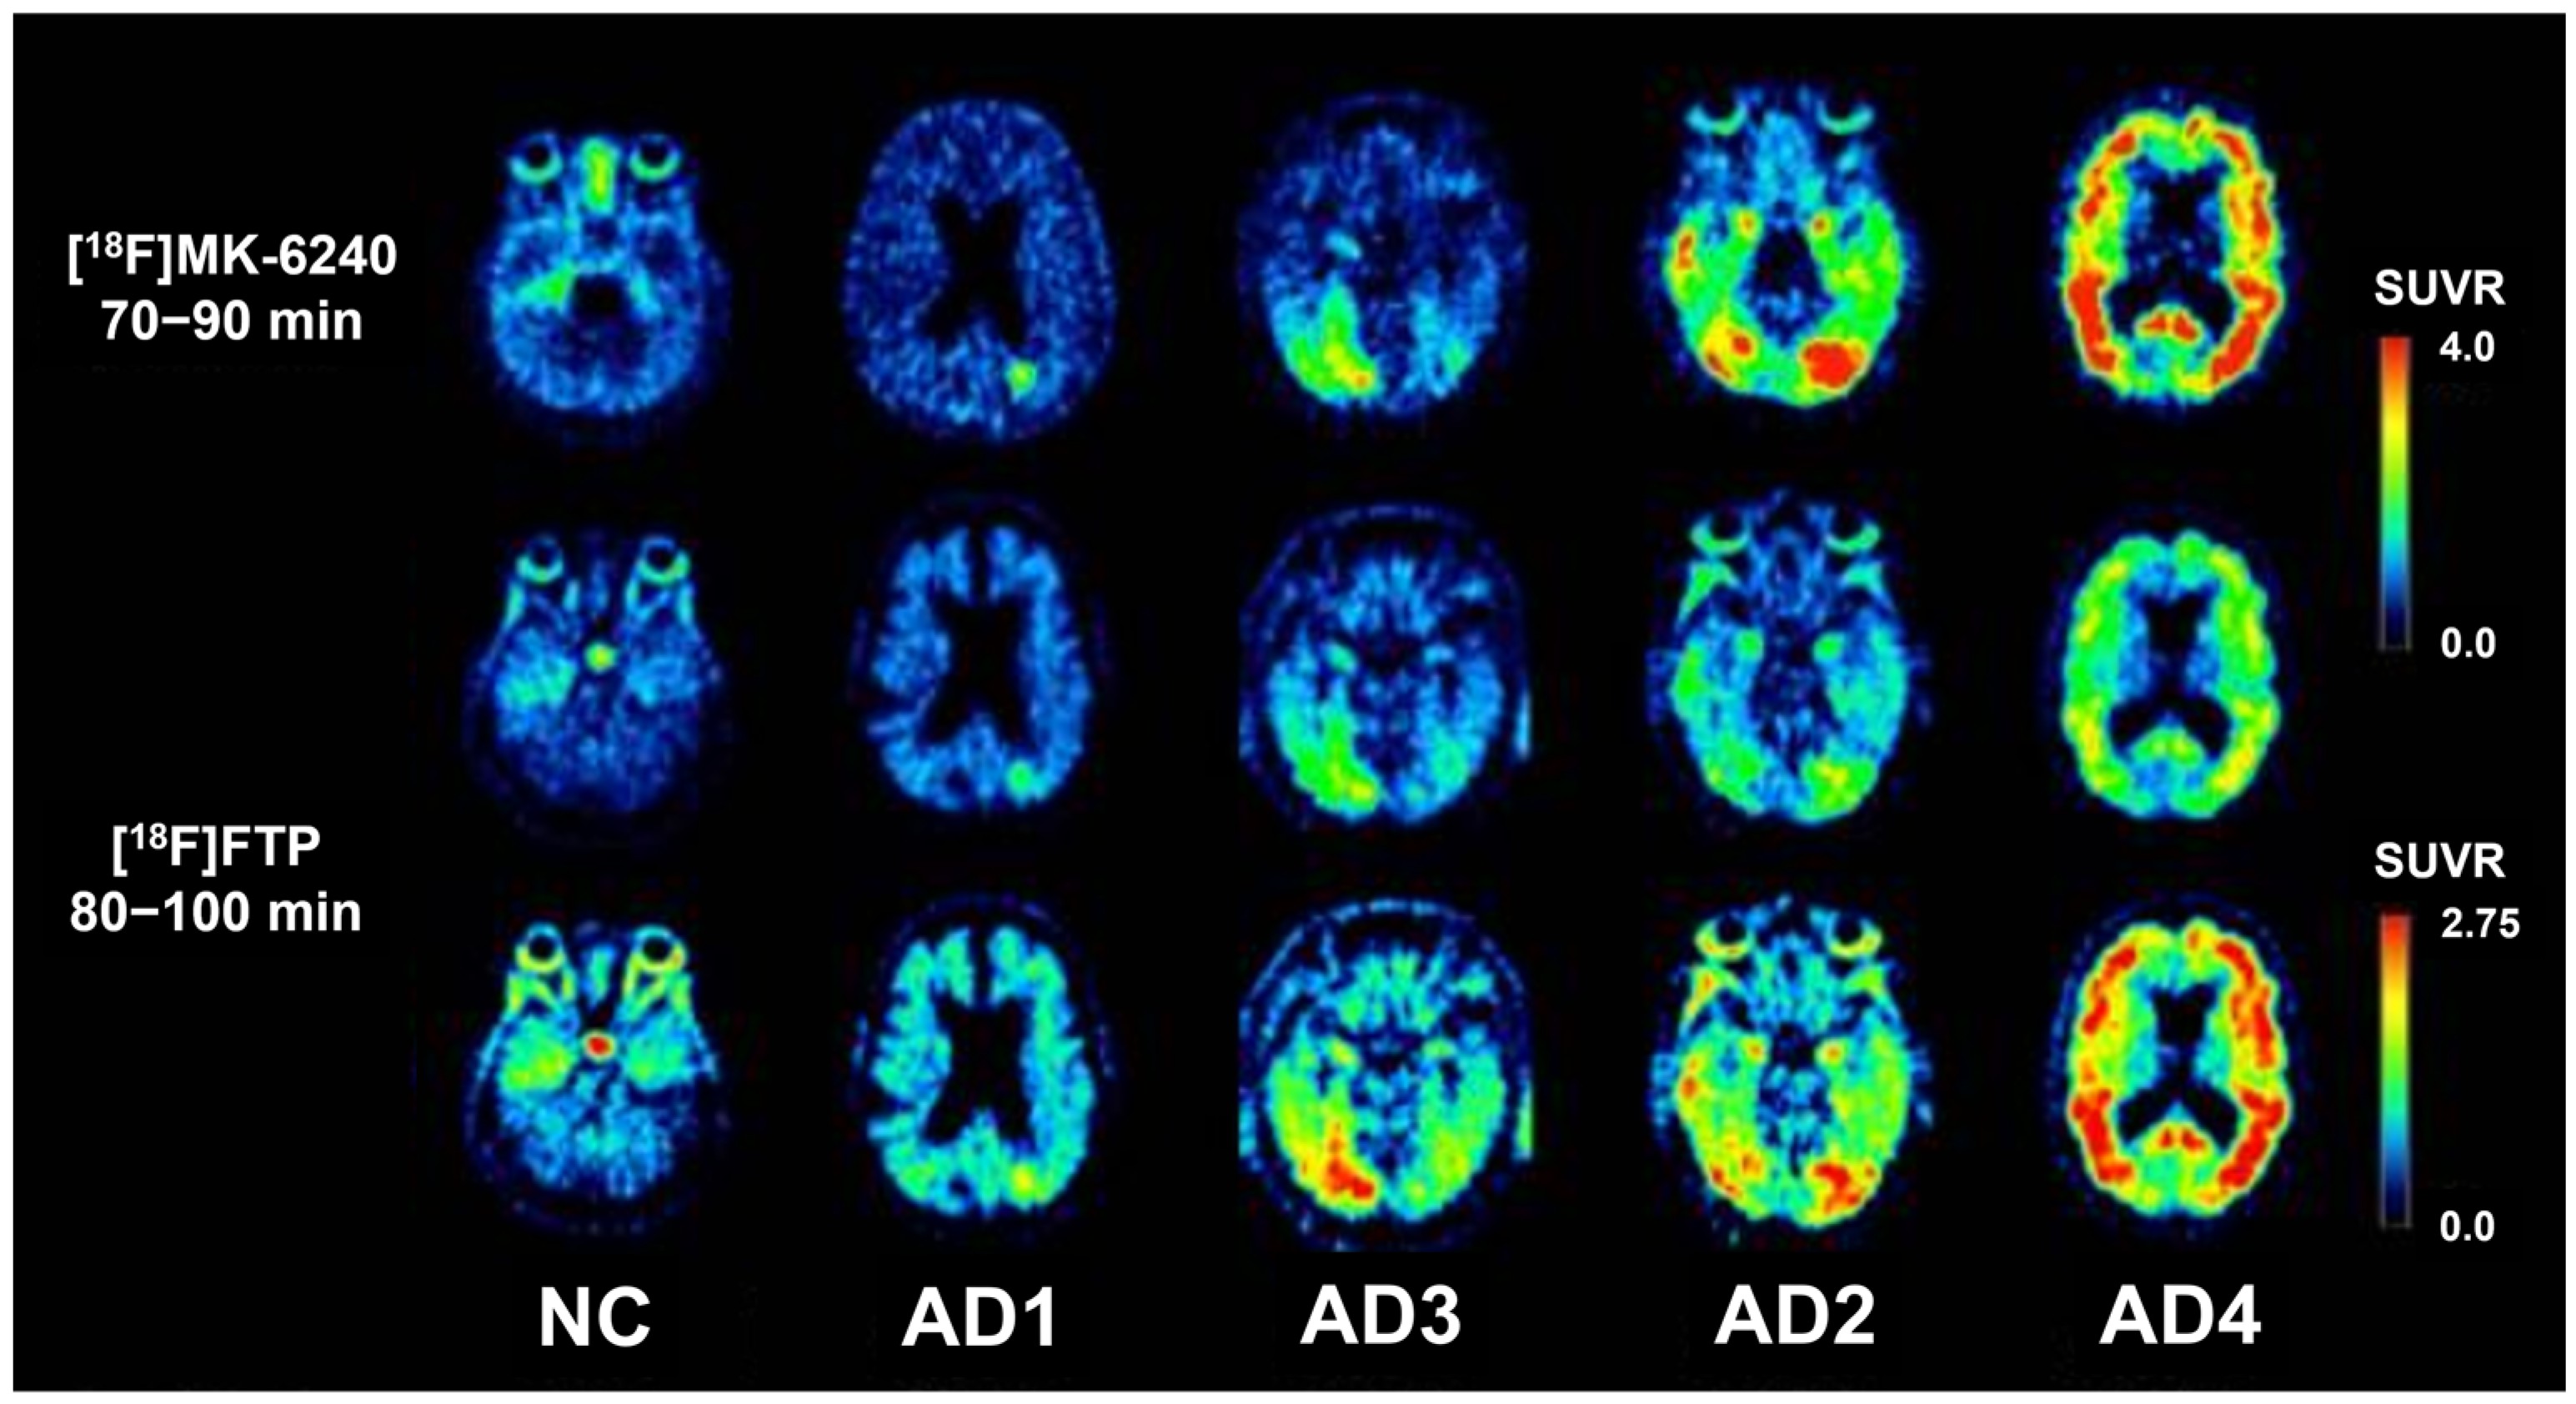

- Vogel, J.W.; Young, A.L.; Oxtoby, N.P.; Smith, R.; Ossenkoppele, R.; Strandberg, O.T.; La Joie, R.; Aksman, L.M.; Grothe, M.J.; Iturria-Medina, Y.; et al. Four distinct trajectories of tau deposition identified in Alzheimer’s disease. Nat. Med. 2021, 27, 871–881. [Google Scholar] [CrossRef]

- Ossenkoppele, R.; Lyoo, C.H.; Sudre, C.H.; van Westen, D.; Cho, H.; Ryu, Y.H.; Choi, J.Y.; Smith, R.; Strandberg, O.; Palmqvist, S.; et al. Distinct tau PET patterns in atrophy-defined subtypes of Alzheimer’s disease. Alzheimer’s Dement. J. Alzheimer’s Assoc. 2020, 16, 335–344. [Google Scholar] [CrossRef] [PubMed]